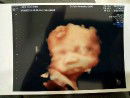

USG 4D

Sejak awal hamil udah di niatin banget buat USG 4D di usia kehamilan 7 bulan. Beberapa bulan sebelum masuk usia kandungan 7 bulan aku sempet was was, coz si dd utun ini selalu aja ngumpetin mukanya kl pas di USG biasa. Dan akhirnya kejadian juga deh pas kmrn USG 4D tangannya dia tutupin ke mukanya ?. Agak kecewa tapi untungnya dokternya sabar banget, sambil nunggu dokter cari2 posisi supaya muka dd utun bisa keliatan, aku coba ajak dia ngobrol aku bilang "De mamah sm papah mau liat mukanya sebentar ya, boleh ya, sebentar aja" Eh Alhamdulillah ga lama tangannya dia pindah ??. Bunda disini ada yg USG 4D juga? Share u foto hasil USG nya pasti lucu2 ??